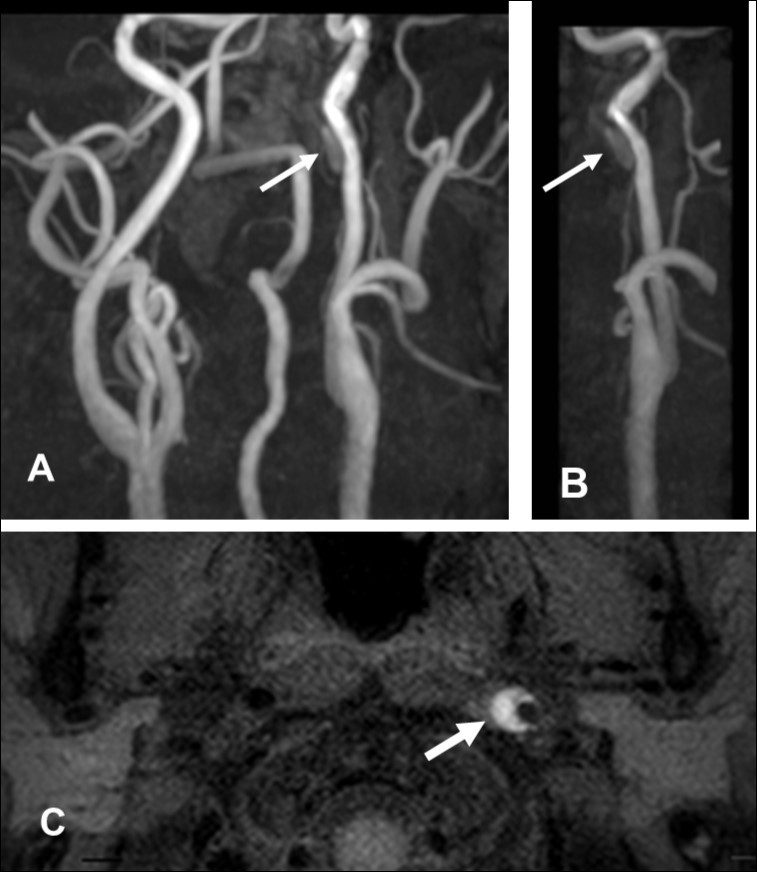

This 43-year-old Japanese male presented with right hand dysesthesia. He has not recognized his neck pain and Horner’s syndrome( oculosympathetic palsy). Magnetic resonance imaging(MRI) performed on a 3T TX scanner (Philips Achieva, The Netherlands) demonstrated dissection of the left cervical carotid artery (CCA; Figure 1A,1B ); no ischemic area was detected in the left cerebral brain. Axial section views of the CCA segment revealed a typical crescent hematoma; a bright, hyper-intense circle representing the narrowed arterial lumen was visualized. A T1-volumetric isotropic turbo spin echo acquisition (VISTA) sequence resulted in the diagnosis of dissection of the CS-ICA (Figure 1C). He had no conventional stroke risk factors such as hypertension, diabetes, hyperlipidemia, a history of cardiac valvular disease, arterial fibrillation, or features of inherited connective tissue disorder. Also absent was a history of arterial trauma and we were unable to identify any etiological factor(s). One week later he developed Gerstman symptoms; border zone ischemia was observed in the left cerebrum (Figure 2-Ic). He was admitted and the administration of antiplatelet agents was started. The left middle cerebral artery (MCA) was supplied via antegrade circulation (Figure 2-Ib) and an increase in the flow-void intensity was noted (compare Figure 1C with Figure 2-Ia). MRI studies acquired one week later revealed spreading of the ischemic area to beyond the watershed zone between the left anterior cerebral artery (ACA) and the MCA, and the MCA and the posterior cerebral artery (PCA) (Figure 2-IIc). The area of dissection had spread from the ICA bifurcation to the top of the ICA. The blood supply to the left MCA territory derived from the circle of Willis (Figure 2-IIb). The flow-void intensity had increased further (compare Figure 2-Ia with Figure 2-IIa). Two weeks after his admission he suddenly experienced complete right-sided hemiparesis with motor aphasia. MRI performed within 45 min demonstrated diffuse ischemia in the left MCA territory (Figure 2-IIIc), the left A1 segment could not be visualized. The left MCA and its A1 segment were completely occluded (Figure 2- IIIb). The flow-void intensity indicated complete occlusion of the true lumen (Figure 2-IIIa). He underwent emergency left superficial temporal artery (STA)-MCA bypass surgery within 6 hours; double anastomosis was successful. External decompression was performed to prevent neurological deterioration due to severe brain swelling. An intensive rehabilitation has been continued for him after operation. His functional independence measure (FIM) score recorded over the course of 4 months showed remarkable improvement ( Figure 3) as did the standard language test for aphasia.

Figure 1.First hospitalization. A. Maximum intensity projection ( MIP )image of arteries in the cervical segment. B. Magnetic resonance angiography of the left carotid artery. C. T1 VISTA sequence. Note the flow void reflective of the narrowed lumen next to intramural hematoma (hyperintense crescent)